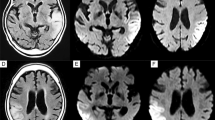

Neuroimaging of patient 2 (adult-onset MELAS). Brain MRIs (a, b) and 123I-IMP SPECT (c) obtained on day 2 of the 2nd SLE show slightly increased DWI/FLAIR signals in the left occipito-temporal cortex and marked hyperperfusion. The MRI/MRA (d–f) obtained on day 6 show increased DWI/FLAIR signals along the cerebral cortex with associated edema and vasodilatation of the left posterior cerebral artery branches. Brain MRIs (g–l) obtained during the active stage of the 3rd SLE show disseminated increased DWI/FLAIR signals confined to the cerebral cortexes. a, d, g–i DWIs, b, e, j–l FLAIR images, c123I-IMP-SPECT, and f MRA

Neuroimaging of patient 11 (adult-onset MELAS). Brain MRIs (a–f) obtained during the 1st SLE show disseminated small increased DWI/FLAIR signals confined to the cerebral cortex with subcortical edema. Note abnormal linear enhancement along the gyri of the affected cortexes (g–i), suggesting the same subacute stage of all disseminated lesions with blood–brain barrier breakdown. Brain MRIs (j–l) obtained at the 2nd SLE show two separate classic SLLs in the right medial frontal lobe (open arrows) and the right occipital lobe (closed arrows), both of which are accompanied by focal hyperperfusion (l). a–c, j DWIs, d–f, k FLAIR images, g–i post-enhanced T1-weighted images, l ASL-MRI

Neuroimaging of patient 8 (pediatric-onset MELAS). Brain MRIs (a–c) obtained on day 3 of the 3rd SLE show multifocal asymmetric increased FLAIR signals disseminated to both cerebral hemispheres, some of which in the right occipital lobe join with edema resulting in continuous lesions resembling classic SLL on FLAIR images. Brain MRIs (d–f) obtained on day 6 of the 4th SLE show a single classic stroke-like lesion in the left occipito-temporo-parietal lobe. Brain MRIs (g–i) obtained on day 3 of the 7th SLE show small increased DWI/FLAIR signals sparsely distributed to the right parietal cortex. Although a cluster of adjoining lesions may resemble classic SLLs on FLAIR image, the imaging pattern is different between classic SLL and a cluster of adjoining lesions. a–f, j–l FLAIR images, and g–i DWIs

Neuroimaging of patient 9 (pediatric-onset MELAS). Brain MRIs (a–f) obtained on day 1 of the 1st SLE show punctate or lineal increased DWI/FLAIR signals along the cerebral cortex of bilateral medial occipital cortexes. Brain MRIs (g–l) obtained on day 2 of the 2nd SLE show numerous punctate lesions on DWI (g–i). Note that a cluster of disseminated lesions on DWI is shown as continuous lesions resembling classic SLLs on FLAIR images (j–l); however, the imaging pattern is different from classic lesion (see Figs. 1d, e, 3d–f). a–c, g–i DWIs and d–f, j–l FLAIR images

Paroxysmal discharges and focal hyperperfusion were seen in 20 of 24 SLEs (83.3%), and 25 of 26 SLEs (96.2%), respectively. Initial brain lesion spread to adjacent cortex over a few weeks in at least 14 of 44 SLEs (31.8%). Such a progressive spread was more frequently seen in SLEs with delayed-onset seizure than in those without (8/12 vs. 6/32, p = 0.0043) and exclusively in C-SLEs but not in non-classic SLEs (14/29 vs. 0/15, p = 0.0013). Progressive spread was often accompanied by focal hyperperfusion (14/14, 100%) and seizure activity (10/13, 76.9%). A MRA did not show vasospasm but rather vasodilatation of the branches of middle cerebral artery or posterior cerebral artery ipsilateral to acute SLLs in nine SLEs (Fig. 1f). Accordingly, C-SLEs were mainly attributed to single continuous lobular lesions incongruent to vascular territory, extending along the cerebral cortex, and occasionally accompanied by a gradual spread of SLL associated with hyperperfusion and persistent seizure activity, while non-classic SLEs were mainly attributed to multiple sparsely distributed or disseminated small cortical lesions (Figs. 1, 2, 3, 4).

SLEs began with acute onset of symptoms in 42 of 44 SLEs (95.5%), but D-SLEs of 2 adult-onset patients began with ill-defined subacute-onset fluctuating encephalopathy. D-SLEs developed in two adult-onset and two pediatric-onset patients. D-SLEs of the adult-onset patients were characterized by non-specific psychosomatic symptoms such as fatigue, dizziness, headache, decreased concentration, speech alteration, tremor, and disinhibited behaviours. These symptoms were initially thought to be psychogenic or residual non-specific symptoms, resulting in a marked delay of the initiation of therapy; no treatment was initiated until a hospitalization 5 months after the symptoms onset in patient 2. In patient 11, it took 3 months to be recognized as a recurrence of SLEs (Online Resource 1). In patient 11, brain MRIs obtained 16 months after the symptoms onset showed extensive gadolinium enhancement along the gyri of the affected cortexes, indicating not only focal disruption of the BBB, but also same subacute stage of all disseminated lesions (Fig. 2g–i). An EEG also showed periodic synchronous discharges (PSDs) when the patient was being confused (Online Resource 4). While D-SLEs in two pediatric patients began with acute onset of headache and vomiting, both patients were immediately transferred to a hospital and treated with intravenous l-arginine and edaravone on the day of the symptom onset. The clinical pictures of D-SLEs were different between adult-onset and pediatric-onset patients. On brain MRIs, disseminated adjacent small lesions joined with each other causing FLAIR hyperintensity along the cerebral cortex similar to classic SLLs (Fig. 3a–c). A cluster of disseminated spotty DWI hyperintensities was also shown as continuous FLAIR hyperintensities resembling classic SLL (Fig. 4g–l). However, imaging pattern was different between classic SLL and a cluster of adjoining lesions.